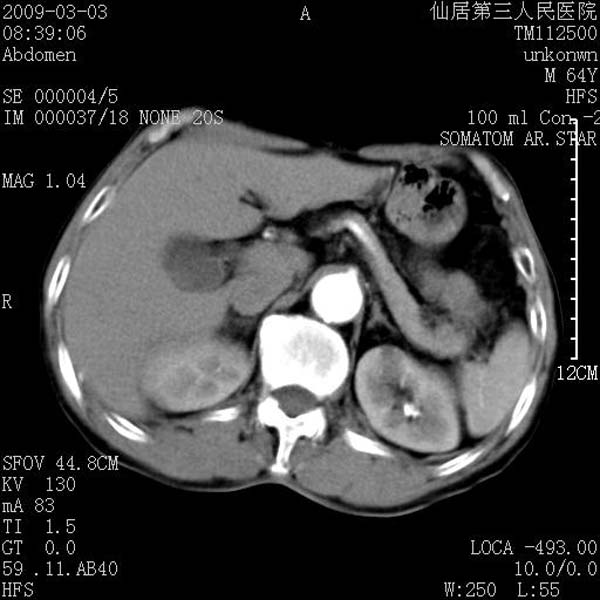

标题: CT18469:男性,64y,体检B超示肝脏低回声肿块,有胃溃疡手术 [打印本页]

患者,男性,64y,体检b超示肝脏低回声肿块,有胃溃疡手术史。

考虑----胃肠道间质瘤可能性大

从平扫及增强的特点来看,支持肝脏腺瘤并出血。

考虑胃间质瘤可能性大。

胃肠道间质瘤!

ct值呢?感觉没强化,象囊性。

考虑肝静脉韧带裂区良性占位性病变(囊肿?)。

考虑肝囊肿并出血可能性大.

考虑高密度囊肿可能性大